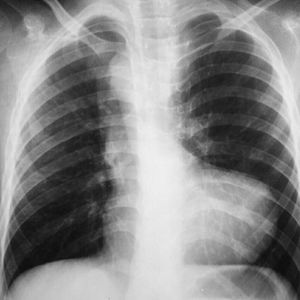

Boot Shaped Heart (Teratology of fallot). TOF is the most common cyanotic congenital heart disorder. It has four cardinal features, Right ventricular hypertrophy, ventricular septal defect, obstriction of right ventricular outflow, and aortic overriding. Plain X-Ray shows boot shaped heart with upturned heart apex. Treatment is by creating a shunt.